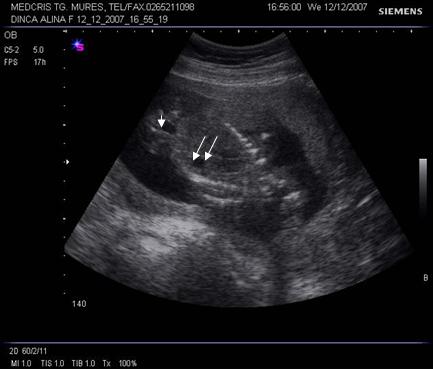

Fig. nr. 188. Sectiune parasagitala fetala cu rinichi in axul longitudinal ( linia)